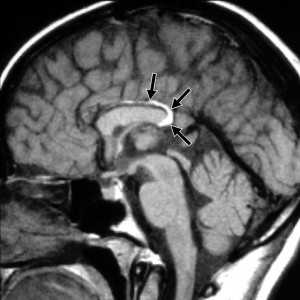

МРТ головного мозга. Сагиттальная Т1-взвешенная МРТ. Липома мозолистого тела.

Липома представляет собой скопление в субарахноидальном пространстве зачаточных жировых клеток с примесью коллагена. Происходят липомы из остатков примитивной эмбриональной оболочки. Эта мальформация оболочек мозга связана с нарушением дифференцировки мезенхимы на мягкую мозговую оболочку и субарахноидальное пространство. Частота липомы составляет менее 0.5% от внутричерепных образований. Обычно липомы локализуется в мозолистом теле, в межполушарной щели, воронке гипофиза и гипоталамусе, реже вокруг червя мозжечка и пластины четверохолмия и мосто-мозжечковом углу и Липомы мозолистого тела сочетаются с его агенезией и в 60% случаев с распространением на сосудистое сплетение. При МРТ головного мозга липома четко очерчена, без отека вокруг и масс-эффекта, кость не разрушает. Структура образования чаще однородная, жировой интенсивности сигнала - то есть выраженно гиперинтенсивная на Т1-взвешенных МРТ и немного менее интенсивная по отношению к ликвору на Т2-взвешенных МРТ. Иногда встречаются неоднородные липомы с участками низкого сигнала от кальцинатов и сосудов, проходящих ее насквозь. При сомнениях в диагнозе надо выполнить МРТ головного мозга с подавлением жира или можно сделать КТ. На КТ липома всегда резко гиподенсна и может содержать включения кальция.